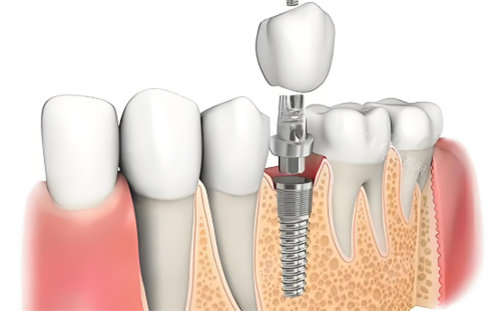

登腾种植体在临床应用中表现出几个显著特点。首先,其双螺纹设计提供了较好的初期稳定性,这对于骨条件良好的患者来说是一个优势。这种设计使得种植体在植入后能够更快地与骨组织结合,为后续修复奠定基础。

丽维思种植体在设计上更在意美学结果。其2.5mm直径的超窄径植体特别适合前牙区的修复,可以减少对邻牙的磨损。此外,该种植体的四级纯钛基台还配备了粉色仿龈瓷,能够更好地模拟天然牙龈的外观,提升整体美观度。

选择种植体时,首先需要考虑修复的位置。如果是后牙区的修复,登腾可能更为适合,因为其稳定性和性价比在后牙区更为重要。而对于前牙区,特别是对美观要求较高的患者,丽维思可能是更好的选择。